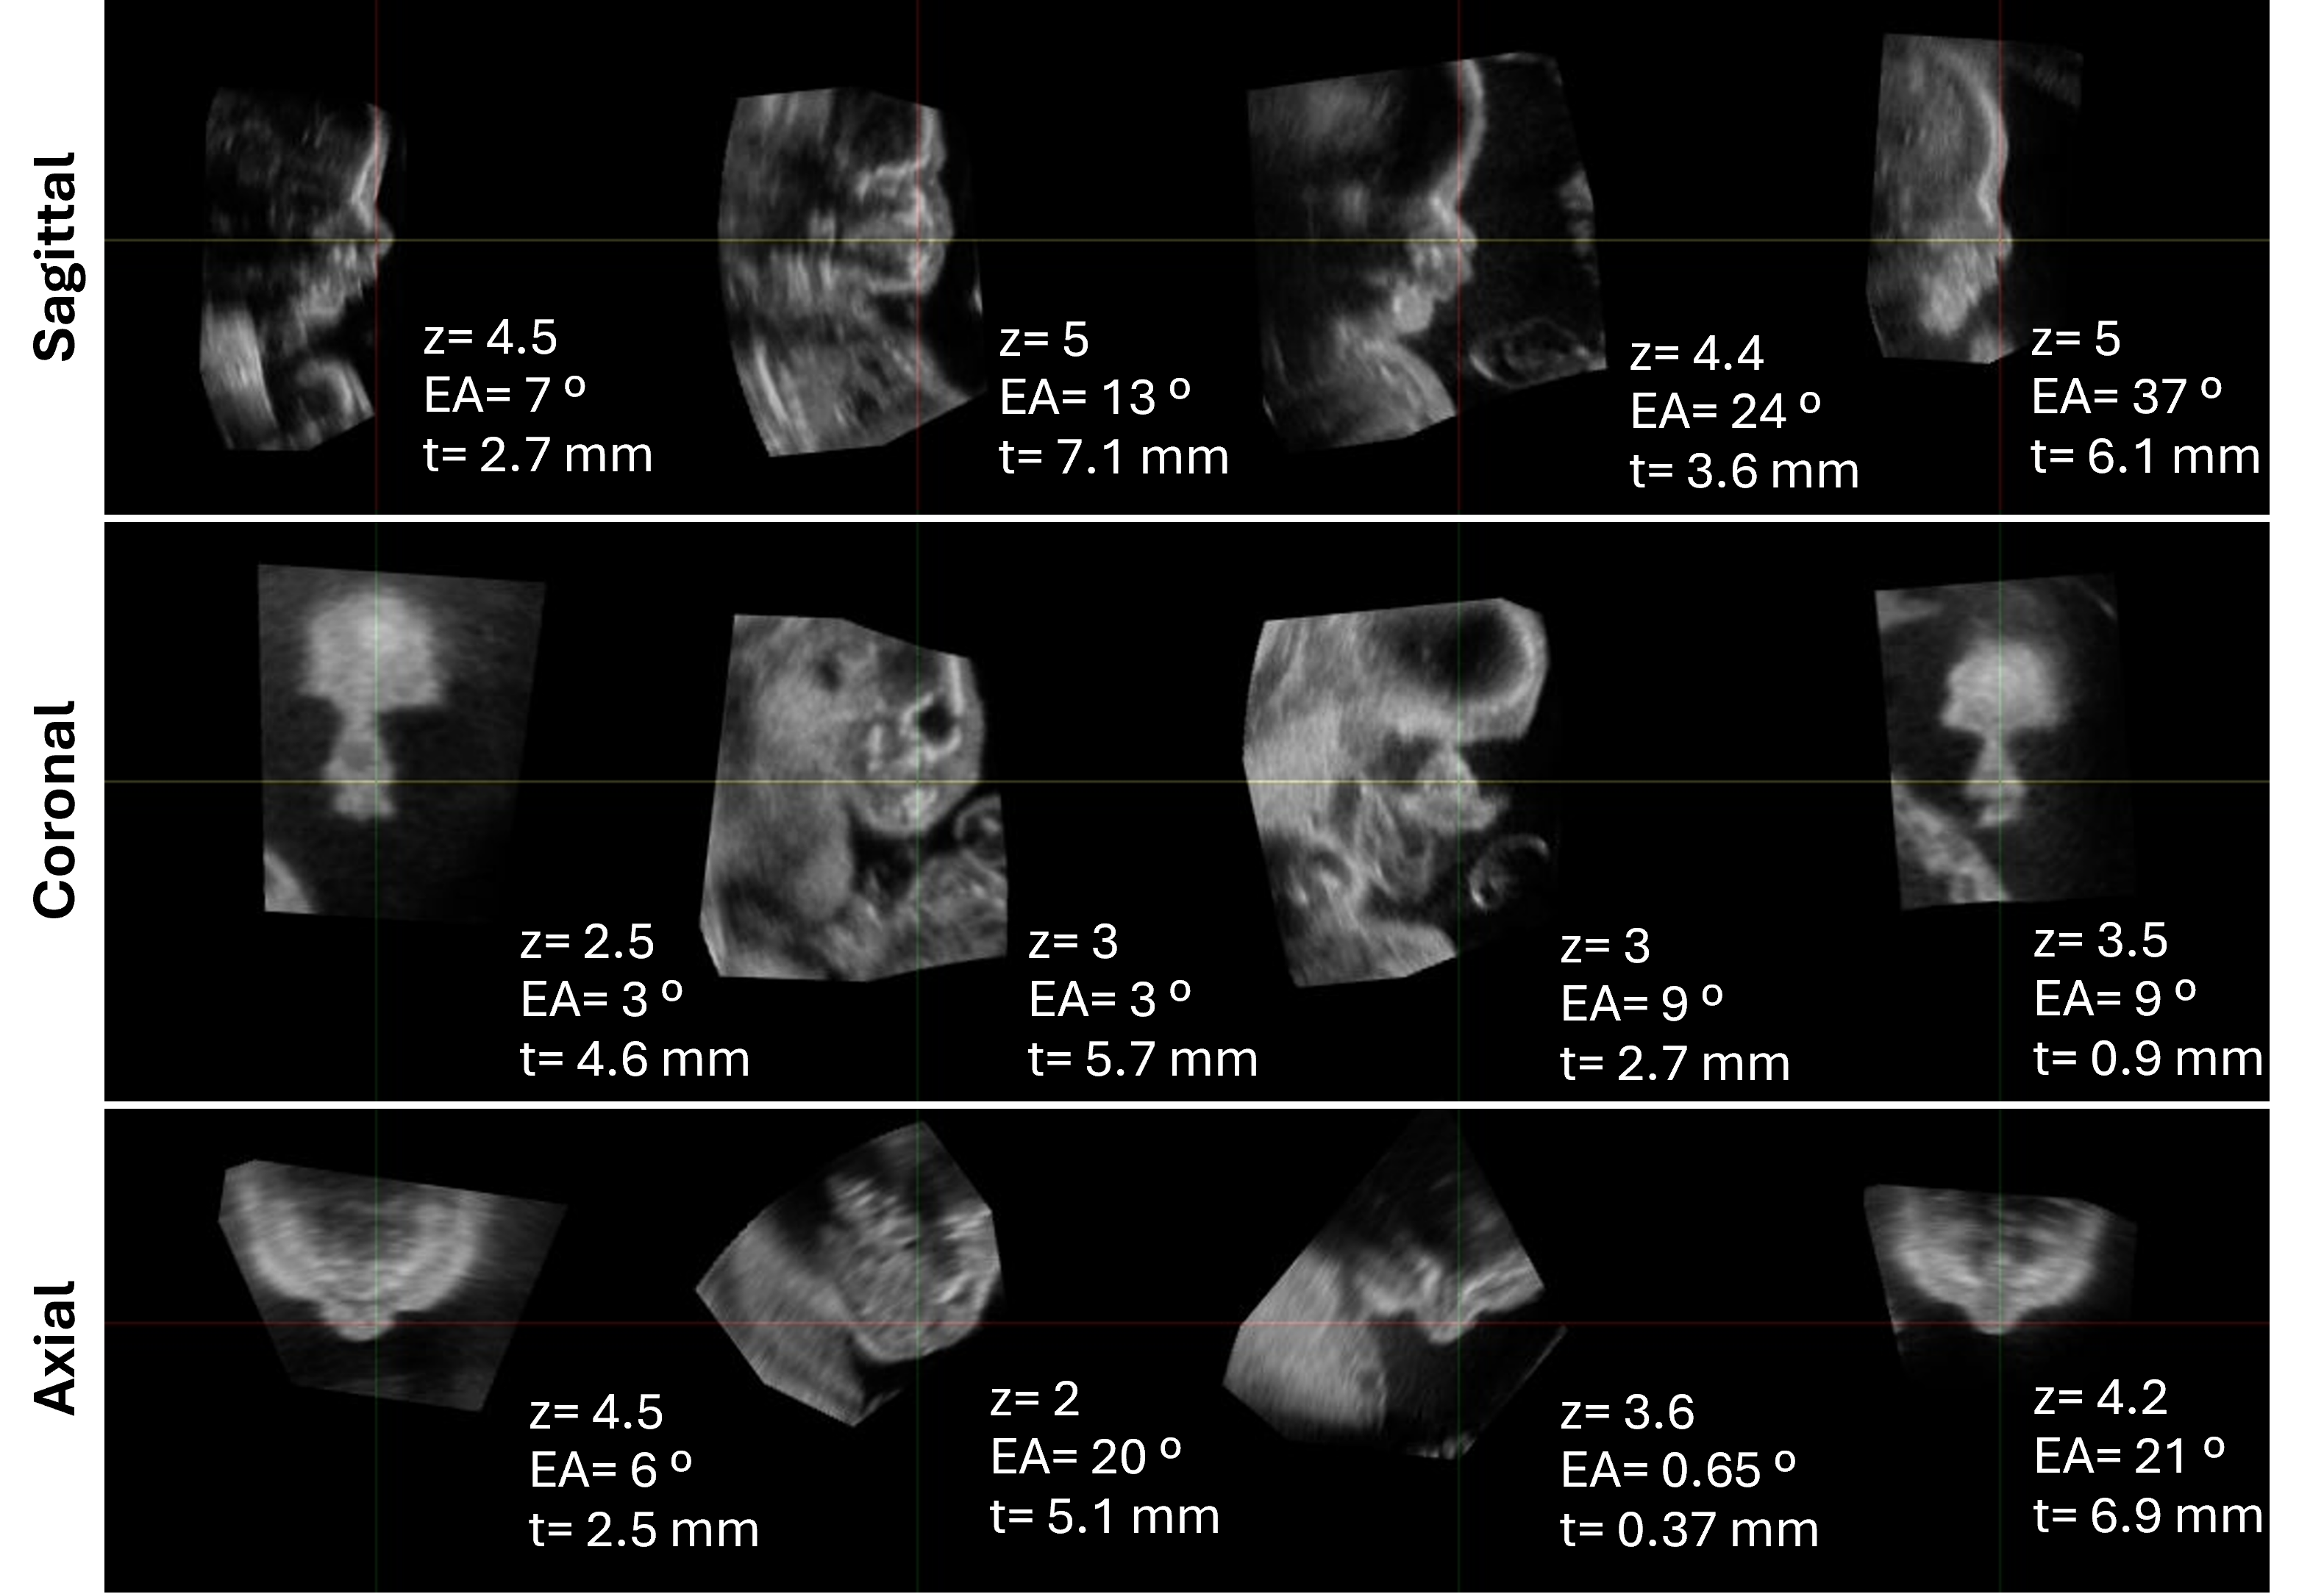

Refer to caption

Figure 5: 3DFETUS performance on the test set. Displayed are 2D planes from three different test subjects representing high, average, and low performance of the proposed 3DFEUS method. For each subject, the Euclidean angle (EA, in degrees) and translation error (tt, in mm) are reported with respect to the ground truth (GT). The mean quality score (zz), as assigned by clinicians, is also indicated.